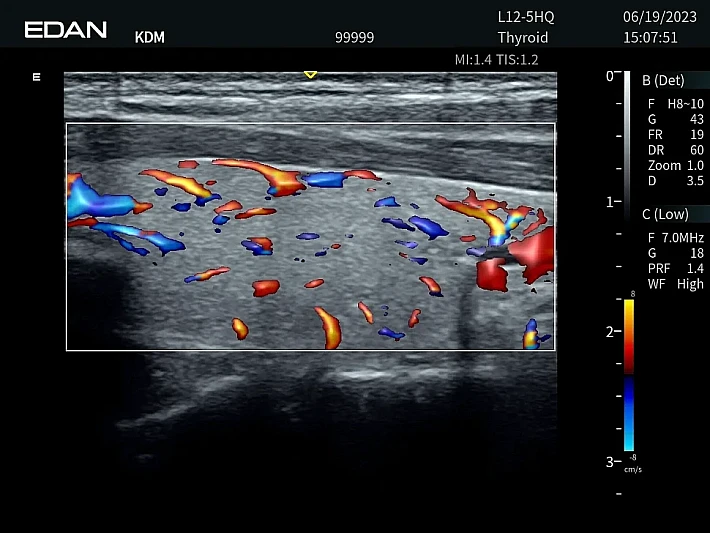

Медицинское оборудование и сервисное обслуживание